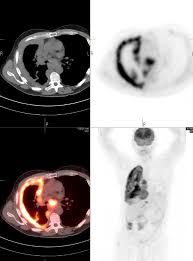

Combining a pet scan with an mri or ct scan can help make the images easier to interpret.

European journal of nuclear medicine and molecular imaging, 2014. Given the presence of the mesothelium in different parts of the body, mesothelioma can arise in various locations 17:. At left is a ct scan, while the center image is a pet scan. Sensitivity, specificity and accuracy were respectively 86, 89 and 87%; The tumor originates from cells of the visceral or parietal pleural and is linked to asbestos exposure with a median latency of 44.6 years .due to the latency between exposure and onset of mesothelioma and the ongoing use of asbestos in parts of the world, the incidence is expected to rise. Current perspectives maria bonomi,1 costantino de filippis,2 egesta lopci,3 letizia gianoncelli,1 giovanna rizzardi,4 eleonora cerchiaro,1 luigi bortolotti,4 alessandro zanello,2 giovanni luca ceresoli1 1department of oncology, thoracic and gu oncology unit, 2department of radiology, cliniche humanitas gavazzeni, bergamo, 3nuclear medicine. Kazuhiro kitajima, hidetoshi matsuo, atsushi kono, kozo kuribayashi, takashi kijima, masaki hashimoto, seiki hasegawa, takamichi murakami, koichiro yamakado. The qualitative assessment was statistically different (p=0.0020, χ). Have been diagnosed with mesothelioma, your doctor may use this test to see if the cancer has spread to lymph nodes or other parts of the body. pet scans are often paired with ct scans to provide doctors with the most accurate view of a patient's body: A tissue biopsy will finalize whether or not a patient has this cancer. It can help identify the best therapies to control the cancer while maximizing quality. When a ct scan is performed, patients may also undergo a pet scan.

Malignant pleural mesothelioma (mpm) is the most common, whereas malignant peritoneal mesothelioma accounts only for. Xie peng 1, wang wei 2 & Introductionmalignant mesothelioma is a neoplasm arising from pleural and peritoneal cells, including pericardium and tunica vaginalis testis, and often characterized by a poor prognosis. You will need to provide a safe and quiet space for your pet, away from active children or other animals while it recovers. A pet scan can also be useful if your doctor thinks the cancer may have spread but doesn't know where. Everything you need know mesothelioma life! Early detection of the fatal and incurable mesothelioma and the subsequent provision of radiation, surgical and palliative asbestosis treatments are known to help a patient to have the best possible chance to extend and improve the quality of life remaining. A pet scan is the best method to determine if mesothelioma has spread to other parts of the body. 191 all treatments were planned based on ct and pet/ct imaging. pet/ct is superior to other imaging modalities for evaluation of distant metastatic disease of mpm given its whole. Tongue metastasis was the first sign of malignant pleural mesothelioma detected by pet/ct. During the diagnostic process, imaging tests help identify tumors, tumor location and metastasis of cancer. When a ct scan is performed, patients may also undergo a pet scan.

Everything you need know mesothelioma life! Some machines can do both a pet and ct scan at the same time. The qualitative assessment was statistically different (p=0.0020, χ). Malignant pleural mesothelioma (mpm) is the most common, whereas malignant peritoneal mesothelioma accounts only for. A short summary of this paper. Doctors can make a metastatic mesothelioma diagnosis through radiology imaging scans such as mri, ct or pet. Kazuhiro kitajima, hidetoshi matsuo, atsushi kono, kozo kuribayashi, takashi kijima, masaki hashimoto, seiki hasegawa, takamichi murakami, koichiro yamakado. Since pet scans only show the where the most tracer fluid was collected, they are an excellent tool for determining how far mesothelioma has spread. European journal of nuclear medicine and molecular imaging, 2014. 191 all treatments were planned based on ct and pet/ct imaging. Doctors analyze imaging scans and tissue or fluid samples to diagnose mesothelioma. Malignant pleural mesothelioma (mpm) is an aggressive thoracic malignancy with a dismal prognosis. ct scans and mris for mesothelioma diagnosis.